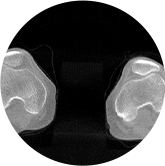

膝關節